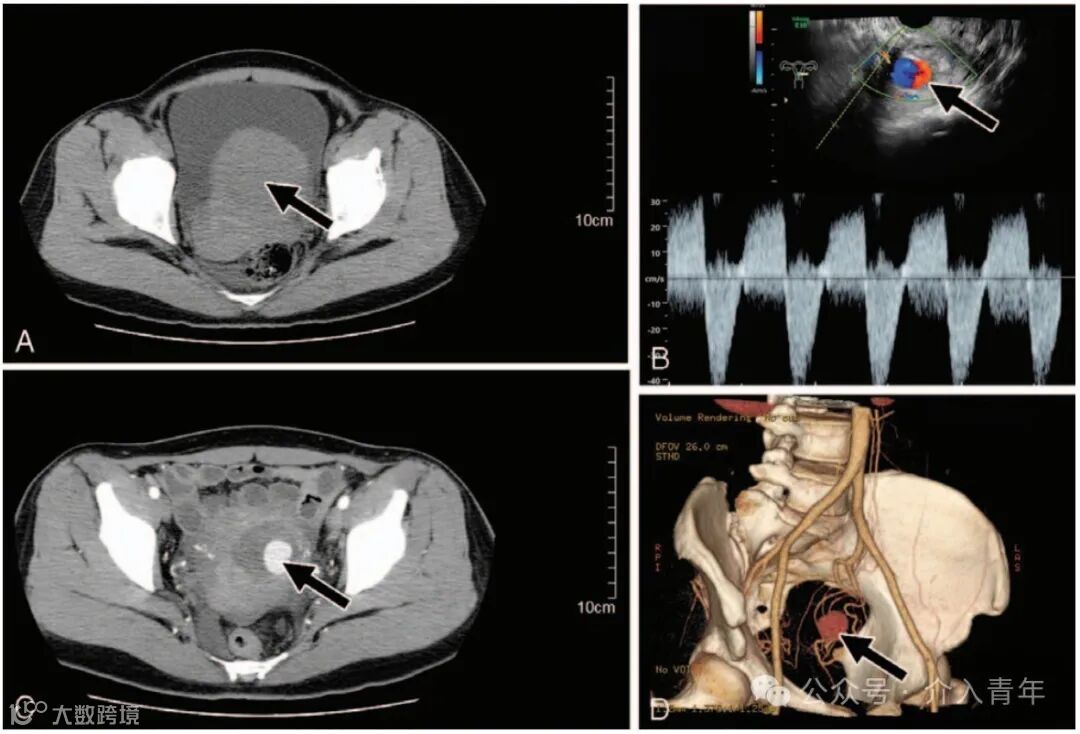

图1:一名47岁患者在腹腔镜子宫肌瘤剔除术后出现子宫动脉假性动脉瘤。

(A)CT显示子宫下段左侧前壁有一个7.0厘米的浆膜下肌瘤(箭头);

(B)术后第19天彩色多普勒超声图像显示肌瘤剔除术后瘢痕处有漩涡状血流(箭头);

(C)CT显示子宫内有强化的假性动脉瘤囊状结构(箭头);

(D)三维计算机断层扫描血管造影显示假性动脉瘤起源于左侧子宫动脉(箭头)[1]。